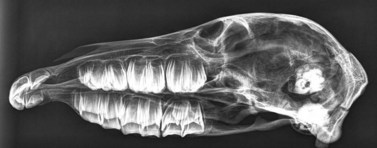

Odontogenic tumors

Tumors of dental-tissue origin are all rare, but may be more common in horses than in other species20 and are discussed in detail in Chapter 11. Five types of odontogenic tumors have been recorded in horses, and their radiological characteristics have been reviewed in detail.21 Ameloblastomas and ameloblastic odontomas can have a similar radiographic appearance.21 They are expansive, soft-tissue opacity masses containing lytic areas and sometimes areas of irregular granular calcification21 and often displace adjacent teeth (Fig. 13.42). Complex and compound odontomas are irregular, tumor-like masses of dental tissues in well differentiated forms (Fig. 13.43). Complex odontomas contain all the elements of a normal tooth but within a disorganized structure, hence radiologically they appear as multiple, small, lobulated radio-opaque masses within a well-defined cyst-like structure.20,21 In contrast, compound odontomas contain an orderly pattern of dental tissues which form recognizable tooth-like structures. Cementomas are very radio-opaque mineralized structures, often rounded in appearance and associated with chronically infected tooth apices (Fig. 13.41F) or their alveoli following extraction of the infected tooth.

image

Fig. 13.42 Ameloblastoma of the rostral mandible, which has displaced the 303 laterally and caused erosion of the 302 and 301 incisors. These tumors can have varying degrees of calcification – this one is well calcified.

(Radiograph courtesy of P.M. Dixon.)

image image image

Fig. 13.43 Radiograph (A) and CT images (B and C) of a compound odontoma in a 2-year-old TB colt.

(Images courtesy of J. Easley.)